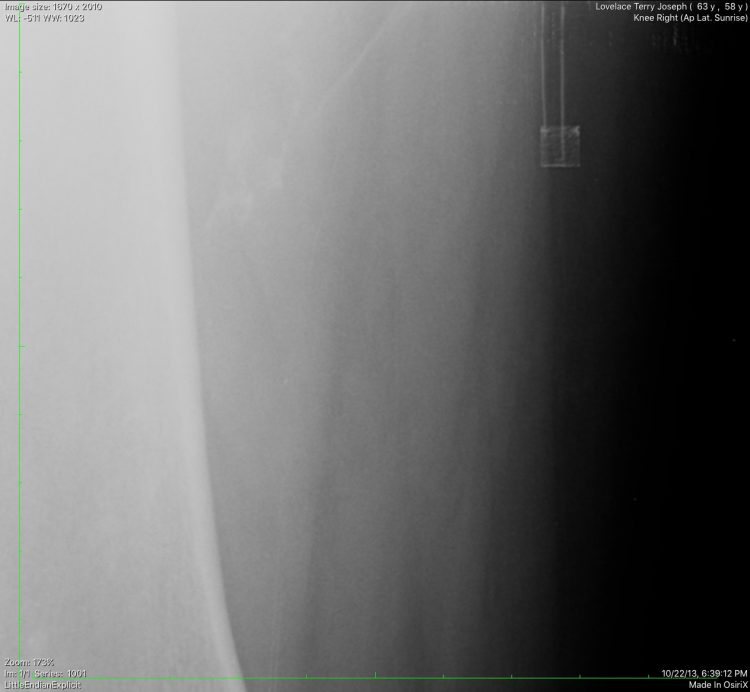

“The female alien threatened first that the thing above my knee (and in left leg Terry knew nothing about) can't be removed and analyzed by terrestrial scientists. She said her 'Host' is going to come and take them from you. They'll take them from you in the middle of the night, and you'll have no pain whatsoever." And her second threat was more direct: 'If you talk about these things, your government will kill you.'”